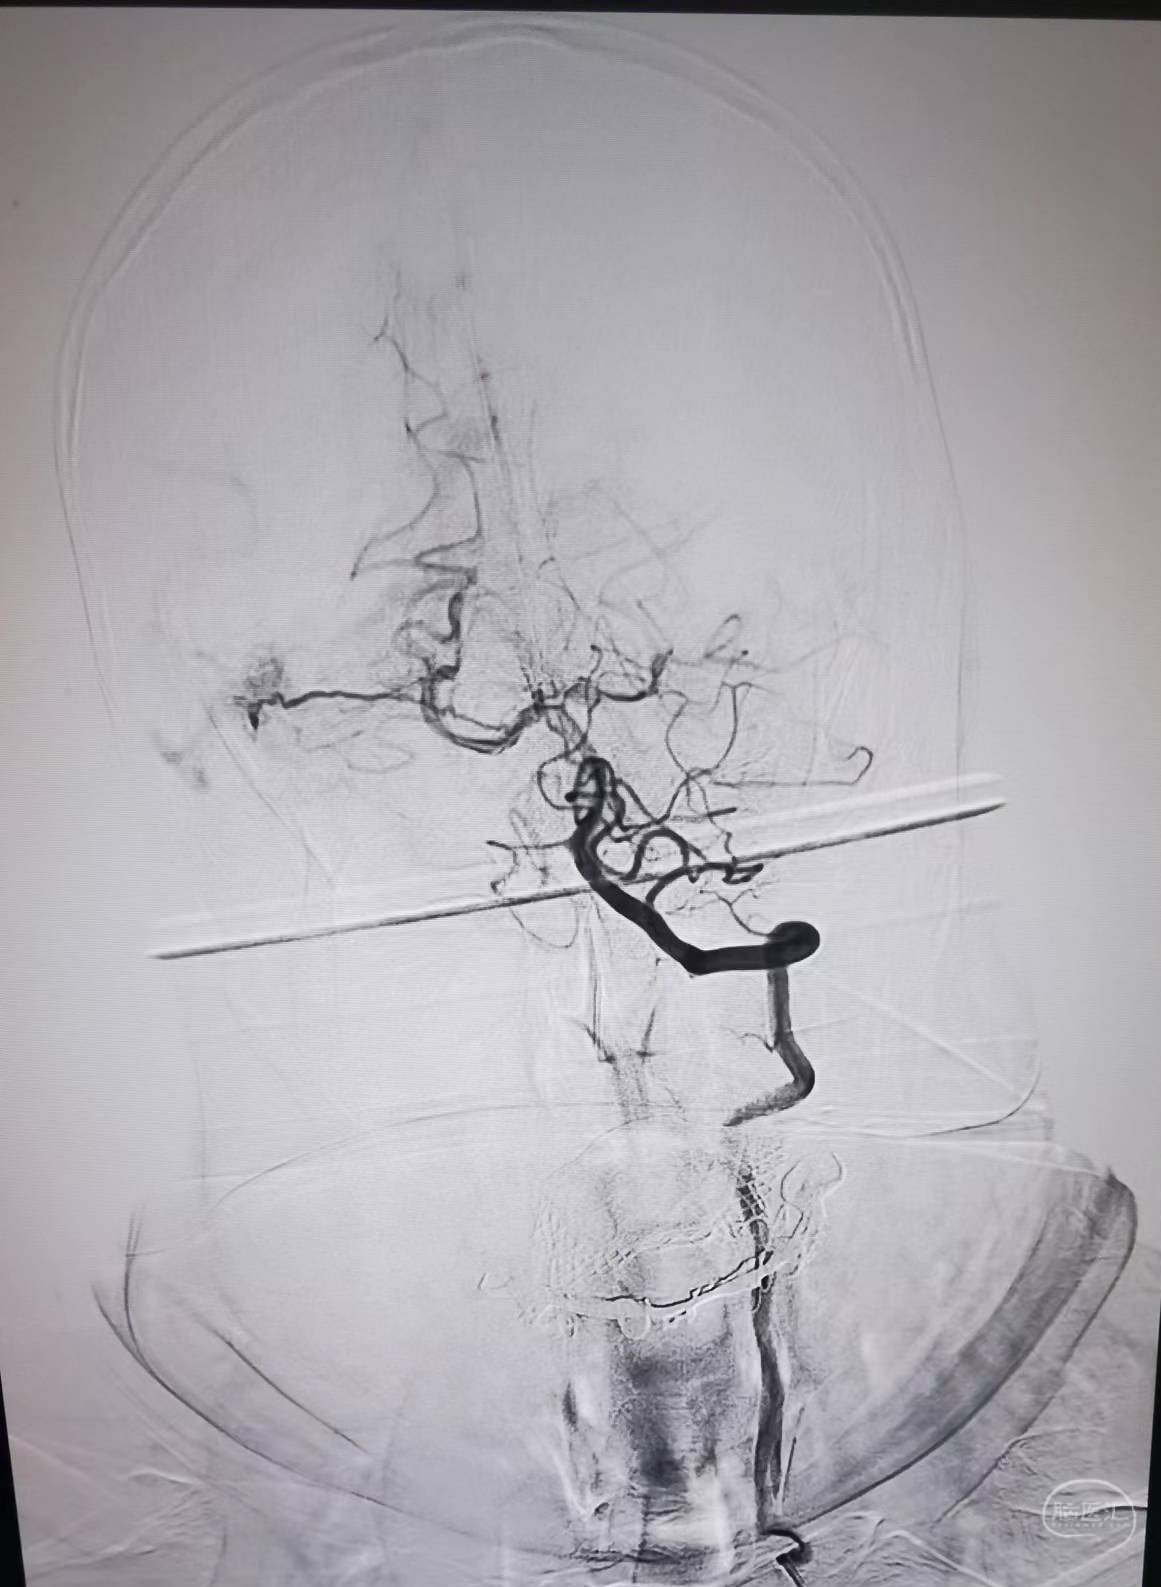

ZXX,M56Y,sah,头颅CTA未见明确动脉瘤。DSA示右侧侧窦区DAVF。

可见颈外动脉多分枝脑膜中动脉、脑膜副动脉、枕动脉、脑膜垂体干、大脑后动脉供血。

造影证实微导管接近瘘口及静脉端,注入onyx胶,其间从左侧股动脉鞘在右侧颈总动脉及右侧椎动脉造影,确认onyx胶已封闭瘘口及所有供血动脉。